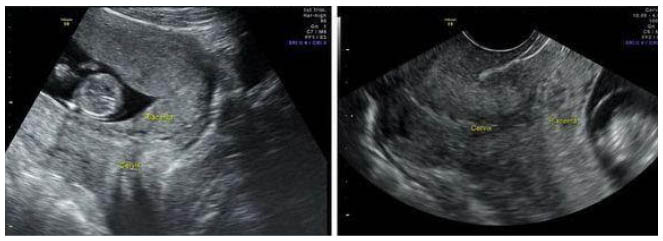

- Данные инструментальных методов исследования — трансабдоминальное/трансвагинальное УЗИ. Позволяет установить факт предлежания плаценты и получить объективные данные о варианте предлежания плаценты, оценить площадь, структуру, размеры и степень зрелости плаценты, степень отслойки, наличие ретроплацентарных гематом, выявить «миграцию плаценты» и ее динамику.

Диагноз ставят начиная с 20 недель, поскольку низкое расположение/предлежания плаценты на ранних сроках беременности могут исчезать.

Место прикрепления

Определяется с помощью УЗИ. Как было сказано выше, при нормальной беременности плацента располагается в теле матки. Иногда при ультразвуковом исследовании в первой половине беременности обнаруживается, что плацента располагается в нижних отделах матки, доходя или даже перекрывая область внутреннего зева шейки матки. В дальнейшем, по мере прогрессирования беременности, плацента чаще всего смещается из нижних отделов матки верх. Однако, если после срока 32 недели плацента по-прежнему перекрывает область внутреннего зева, такое состояние называется * предлежанием плаценты**, что является серьезным осложнением беременности.

Предлежание плаценты может привести к развитию кровотечения, которое может возникать во II-III триместре беременности или во время родов.

Предлежание можно диагностировать сразу после формирования плаценты. Выявить его можно на обычном УЗИ.